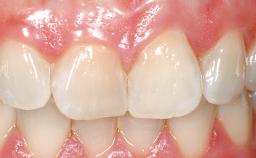

Immediate Flapless Placement of an Implant in a Maxillary Right Lateral Incisor Site

This 43-year-old male patient, a non-smoker, came to our practice because of a fracture of tooth 12 caused by a bicycle accident. Due to the combined para- and infrabony crown and root fracture, tooth extraction, and subsequent implant placement were suggested to the patient as the therapy of choice. The patient had high esthetic expectations with regard to the treatment outcome and asked for an immediate fixed provisional restoration. His individual esthetic risk profile summed up to a medium esthetic risk.

Patient's Esthetic Expectations Low Medium High

Soft Tissue Contour and Volume Ideal